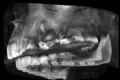

Час назад отвалилась коронка. Ставили ее лет так 10 назад. Я заметил не так давно, что она шаталась, но не придал этому значения. Хотел сейчас пойти в клинику к доктору, который ее ставил, но свободная запись только через два дня.

Нужно срочно спешить или можно все же подождать несколько дней для решения вопроса? Все же хочется к своему доктору. Насколько вообще это серьезно?

10 лет для коронки — это хороший срок службы. Срочной необходимости посетить доктора у Вас нет, думаю два дня ничего не решат. А сохранность данной конструкции зависит от качества лечения и подготовки к протезированию.